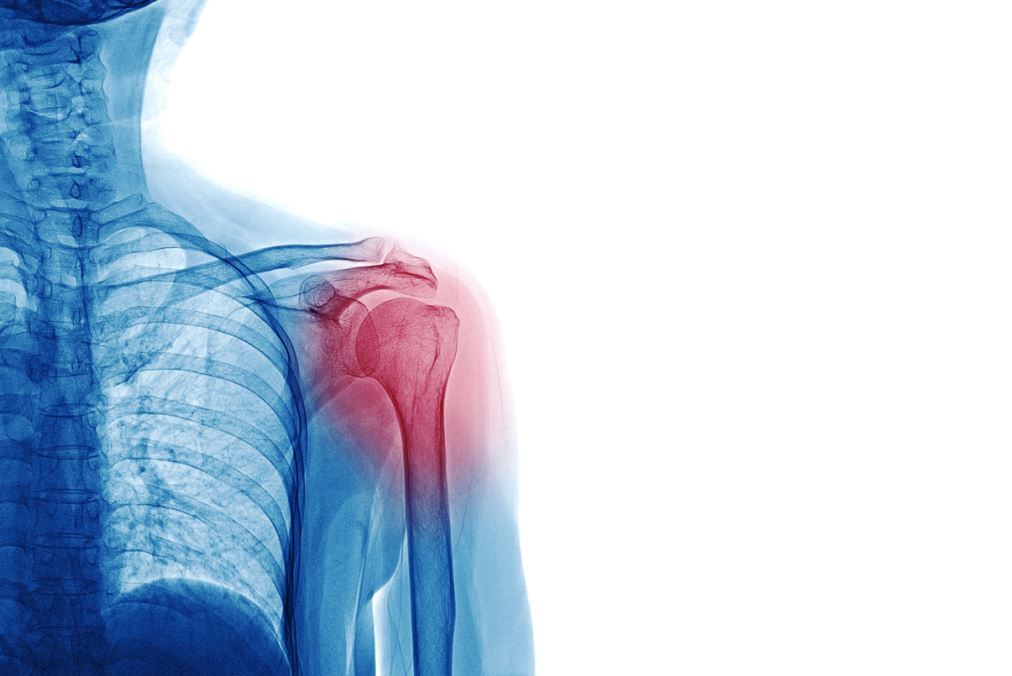

Dislocation

Dislocation is injuries that occur when bone moves out of place in the joint, causing severe pain, swelling, difficulty moving, and often affecting the shoulder, elbow, or knee. At Afaq Medical Care Center in Ibri, we offer immediate and integrated dislocation treatment to relieve pain and restore joint function. Our specialized medical team assists you with an accurate diagnosis and a personalized treatment plan. If you are looking for a reliable treatment for dislocation in Hebrew, then Horizon Center is your destination for the perfect healthcare.

1. Accurate diagnosis: We start with a medical examination with imaging tests such as X-rays to confirm dislocation and rule out associated fractures.